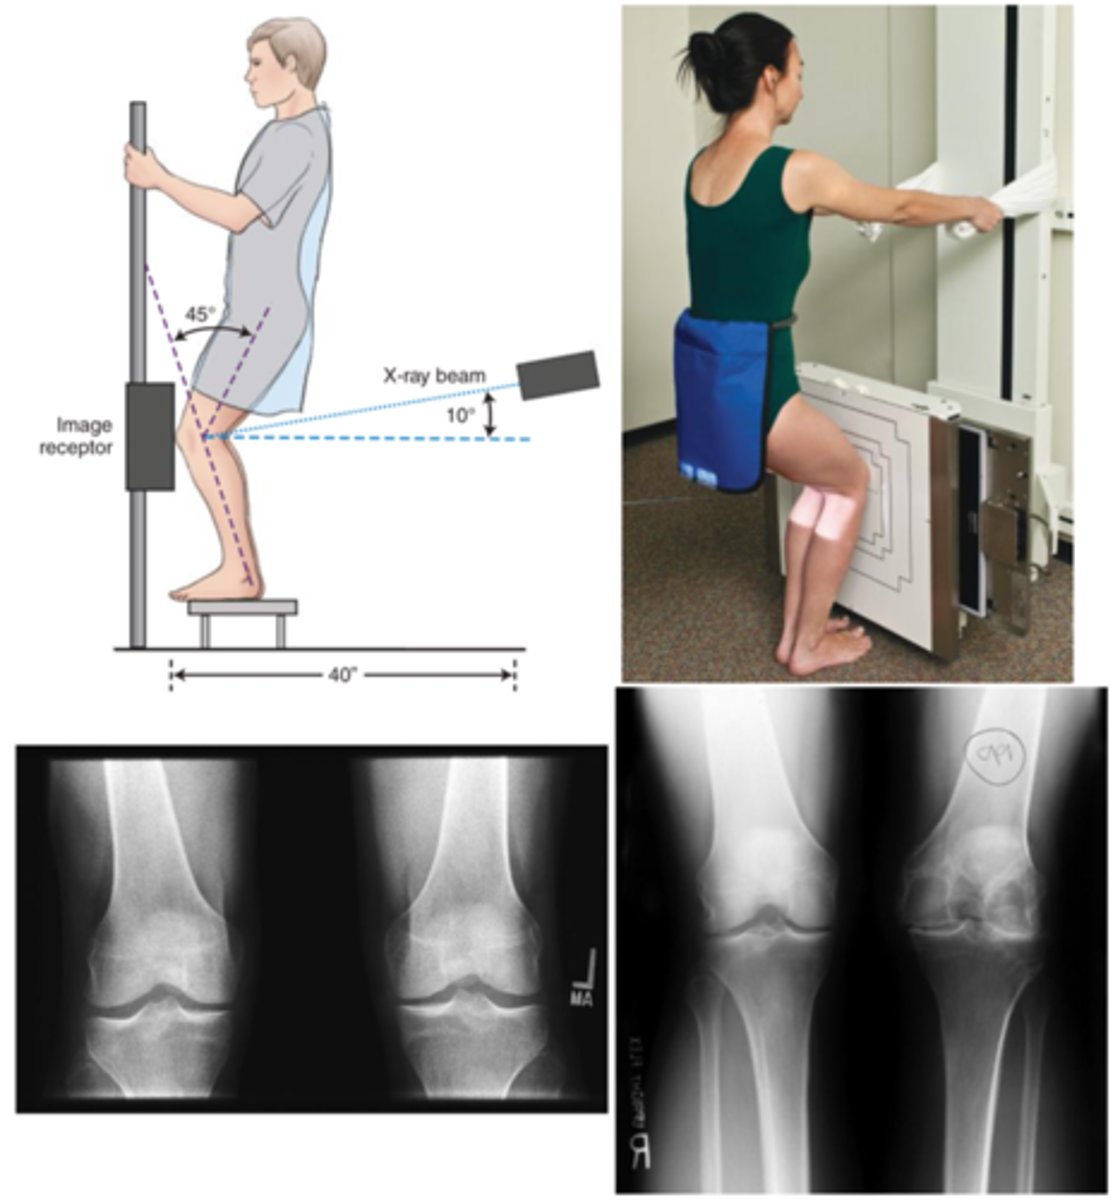

Describe, in detail, how a PATIENT should be positioned for a ROSENBERG KNEE projection.

1. The patient is weight-bearing in a PA position; patient to stand on a stool against the bucky.

2. Tibia should be touching & parallel with the IR.

3. Rotate lower leg to ensure centralisation of the patella.

4. Patient to hold the bucky column and then sit/squat back. Encourage weight distribution to the joint being imaged.

How should we position the X-RAY TUBE when doing a rosenberg projection of the KNEE?

SID

Central ray

Centring point

SID: 100 - 110cm

Central ray: 10 degree cranial angle

Centring point: 1.5cm distal to the apex of the patella